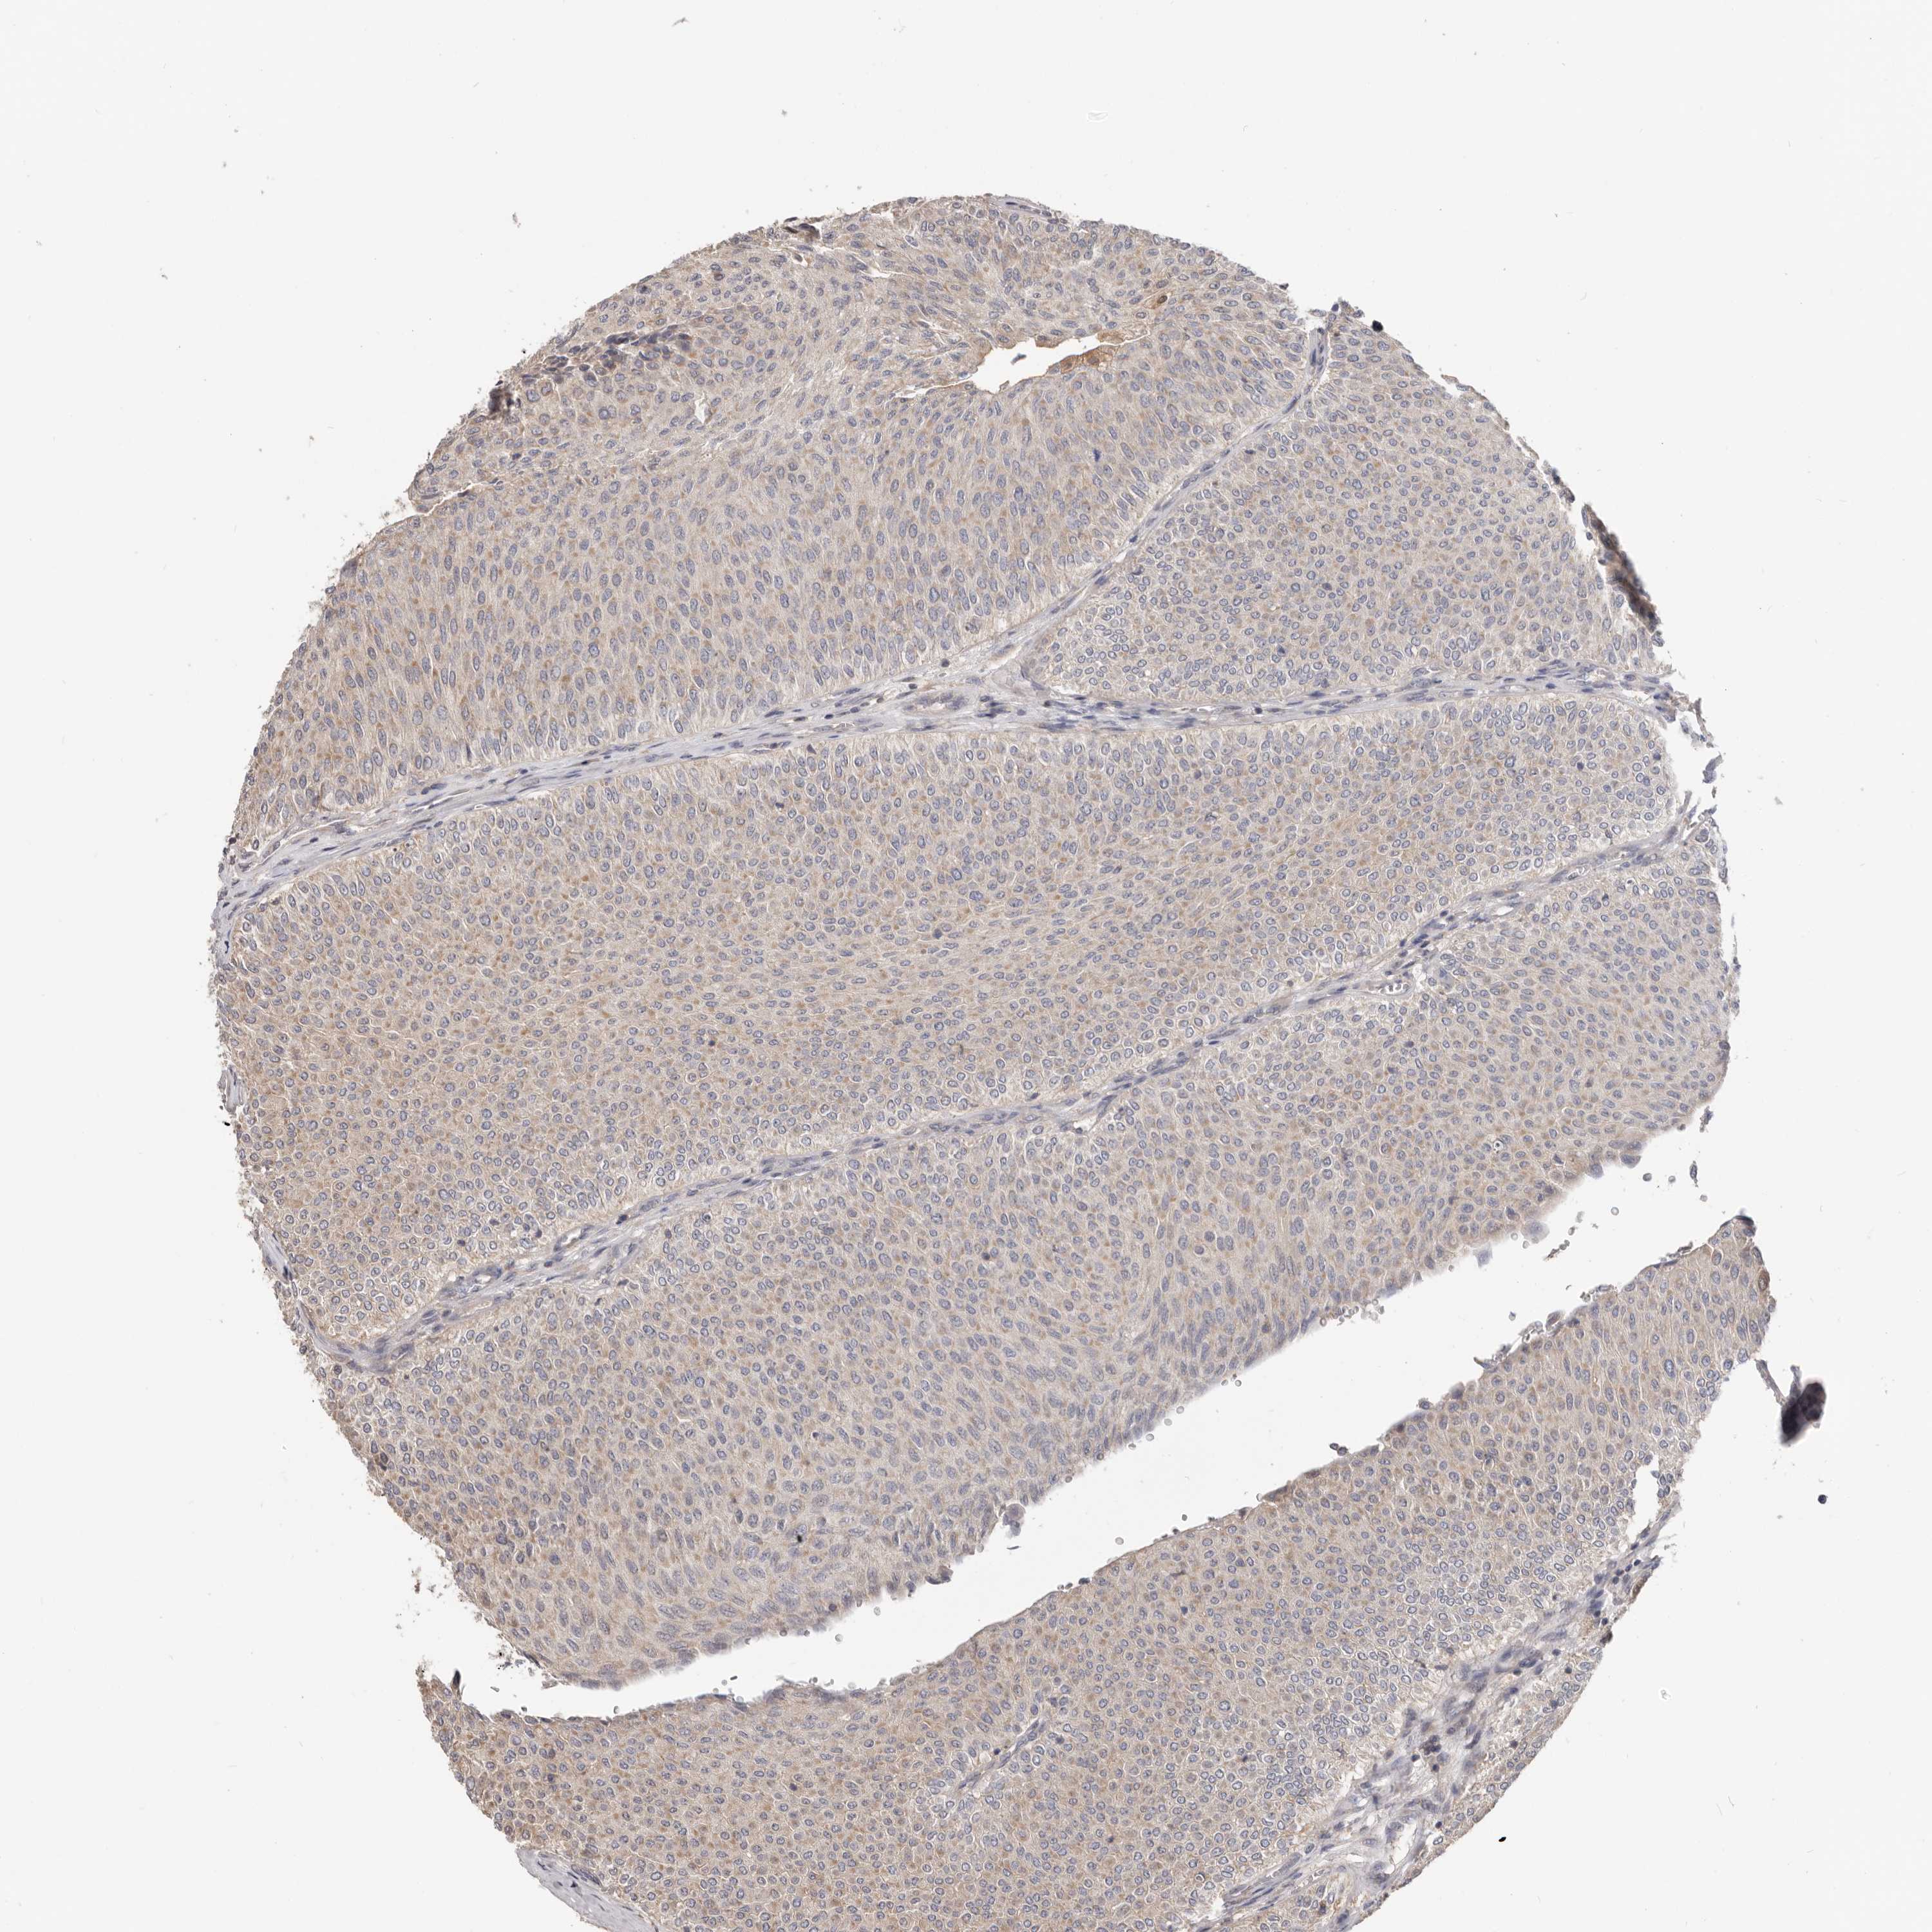

UROTHELIAL CANCER - Protein expressioni

A mouse-over function shows sample information and annotation data. Click on an image to view it in a full screen mode. Samples can be filtered based on level of antibody staining by selecting one or several of the following categories: high, medium, low and not detected. The assay and annotation is described here.

Note that samples used for immunohistochemistry by the Human Protein Atlas do not correspond to samples in the TCGA dataset.

Antibody stainingi

Antibody staining in the annotated cell types in the current human tissue is reported as not detected, low, medium, or high, based on conventional immunohistochemistry profiling in selected tissues. This score is based on the combination of the staining intensity and fraction of stained cells.

Each image is clickable and will lead to virtual microscopy that enables deeper exploration of all samples and also displays staining intensity scores, fraction scores and subcellular localization as well as patient and tissue information for each sample.

Antibody HPA029925

Antibody CAB004490

Staining

High

Medium

Low

Not detected

Intensity

Strong

Moderate

Weak

Negative

Quantity

>75%

75%-25%

<25%

None

Location

Nuclear

Cytoplasmic/membranous

Cytoplasmic/membranous,nuclear

Urothelial carcinoma, Low grade

Urothelial carcinoma, High grade